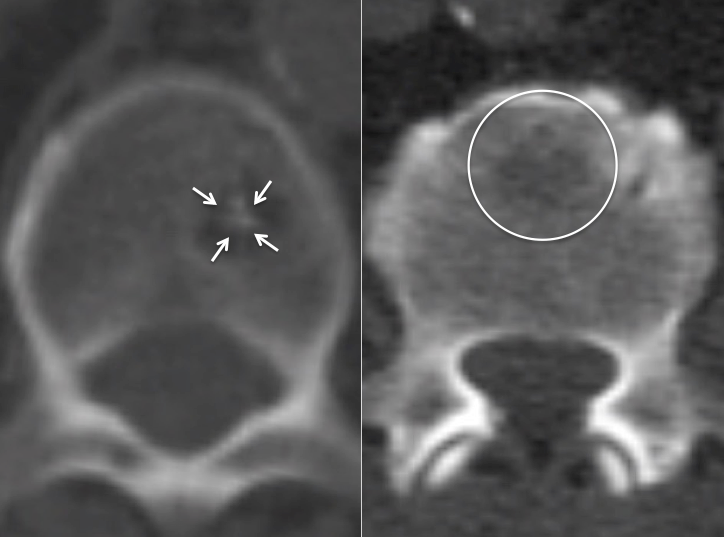

Schmorl’s Node:

A Schmorl’s node is a focal herniation of disc material into a vertebral body. It appears as a rounded lucency in the vertebral body, contiguous with its endplate. The lucency often demonstrates surrounding sclerosis.

While typically non-avid, Schmorl’s nodes can be FDG-avid, occasionally demonstrating even intense metabolic activity. MRI evaluation may occasionally be required to distinguish a hypermetabolic Schmorl’s node from a lytic metastasis.